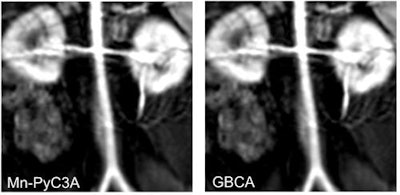

The agent, Mn-PyC3A, has been used in animal studies for contrast enhancement of a baboon's blood vessels and was found to be equivalent to gadolinium-based agents, which carry significant health risks for some patients.

In the current study, the researchers compared Mn-PyC3A with a commonly used GBCA in a baboon model. Each animal underwent two MRI scans under identical conditions -- one with Mn-PyC3A and one with the GBCA. The dosages and imaging protocols were the same as those used for human patients.